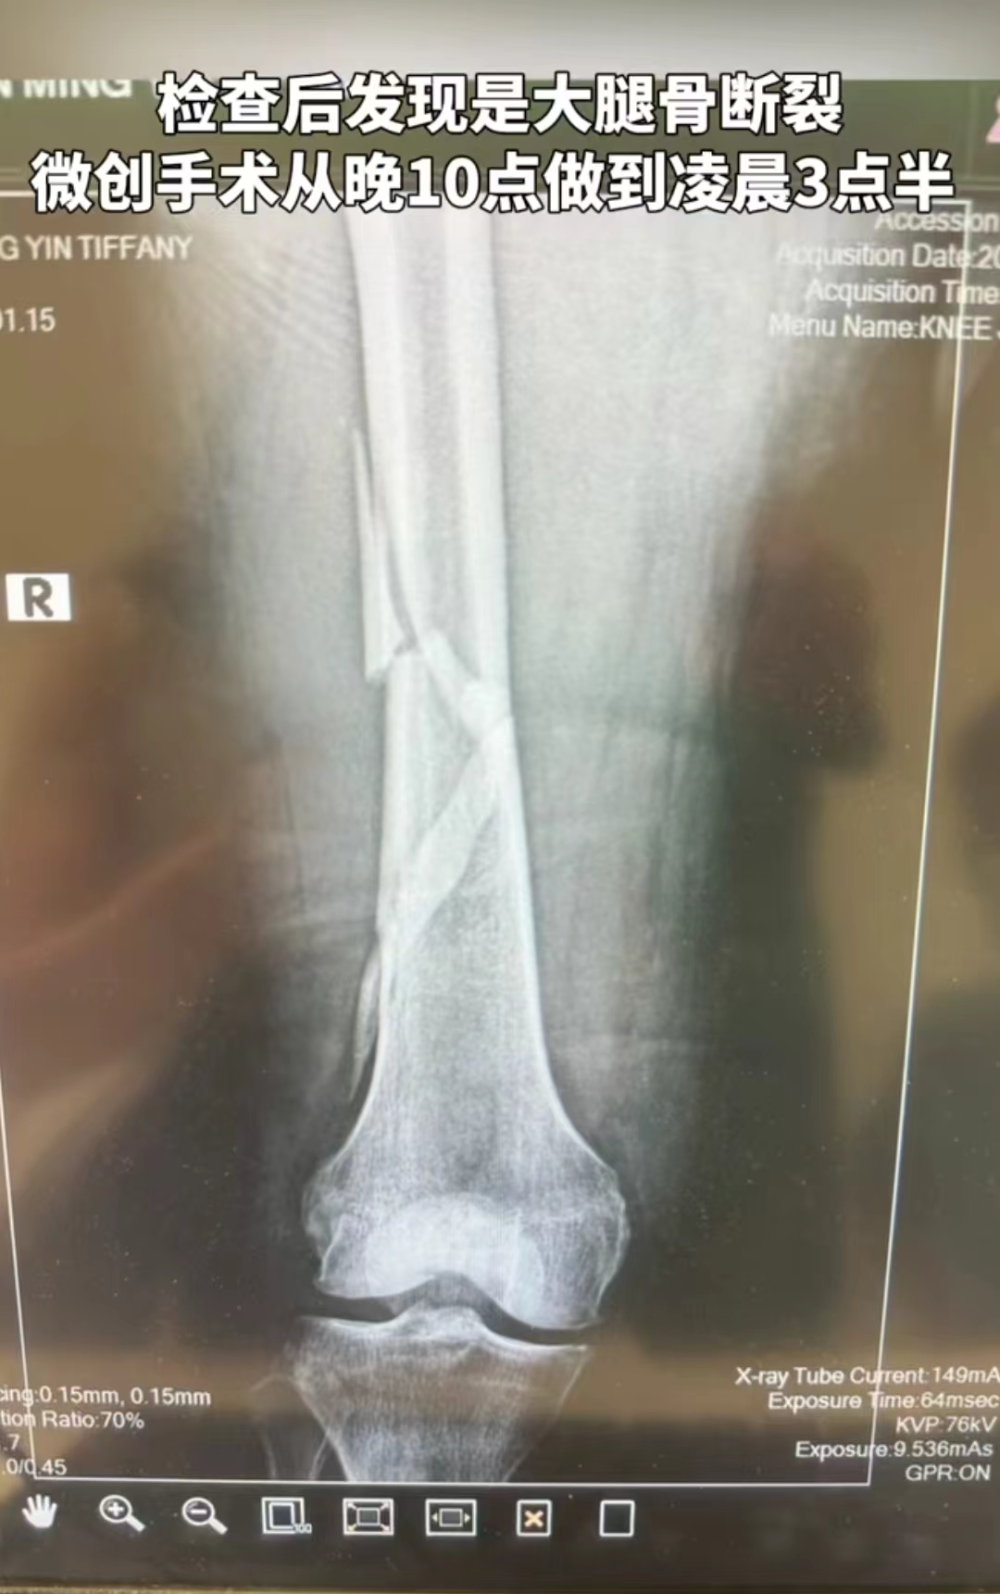

到医院后,通过专业检查,发现她大腿骨断裂,于是做了手术。“整个过程我没流一滴眼泪。现在大腿里有一根很长的钛金属管和四根髓钉。”向太笑称自己现在是名副其实的“钢铁女侠”了。